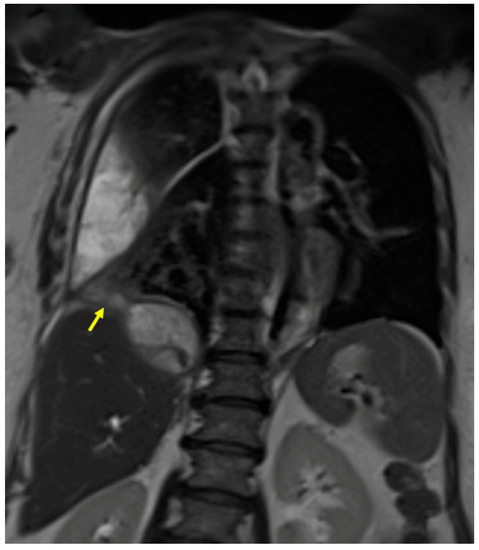

3.1. Case #1: Hepato-Thoracic Fistula